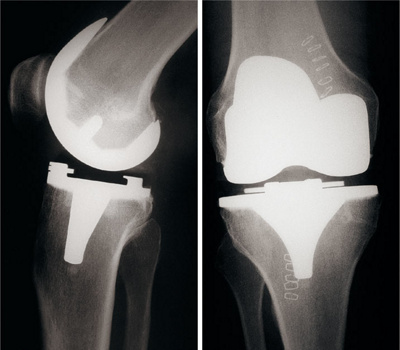

Abb. 1

Die Grösse, Position und Rotation der Kniegelenkprothese werden am Computer für jeden Patienten individuell berechnet.

Abb. 2

Das Ergebnis: Die Kniegelenkprothese steht im perfekten Verhältnis zur Beinachse.